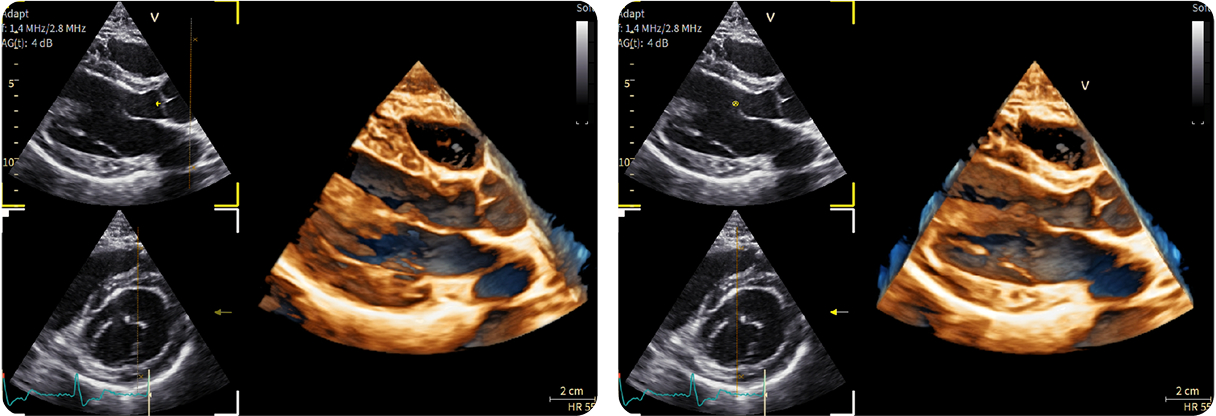

1-Beat Cardiac migliora la qualità diagnostica dell’angio-TC coronarica

L’angio-TC coronarica (CCTA) è uno strumento diagnostico essenziale per l’identificazione delle malattie coronariche, ma la sua affidabilità può essere compromessa nei pazienti con frequenza cardiaca elevata. Grazie ai progressi tecnologici, la modalità 1-Beat Cardiac consente ora di ottenere immagini di alta qualità anche in condizioni di elevata frequenza cardiaca.